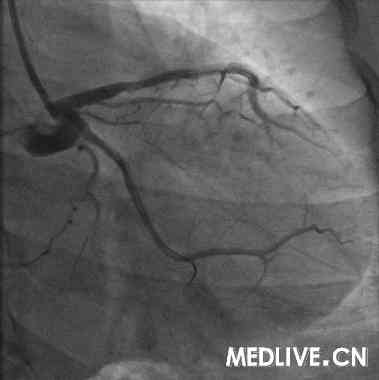

术前血管造影(附图):

冠造结果(图2-4):回旋支中段100%闭塞;右冠中段100%,并见大量血栓影;前降支中段不规则狭窄50%。结合临床,考虑右冠为急性心肌梗死相关冠脉,应首先对其进行急诊介入治疗。